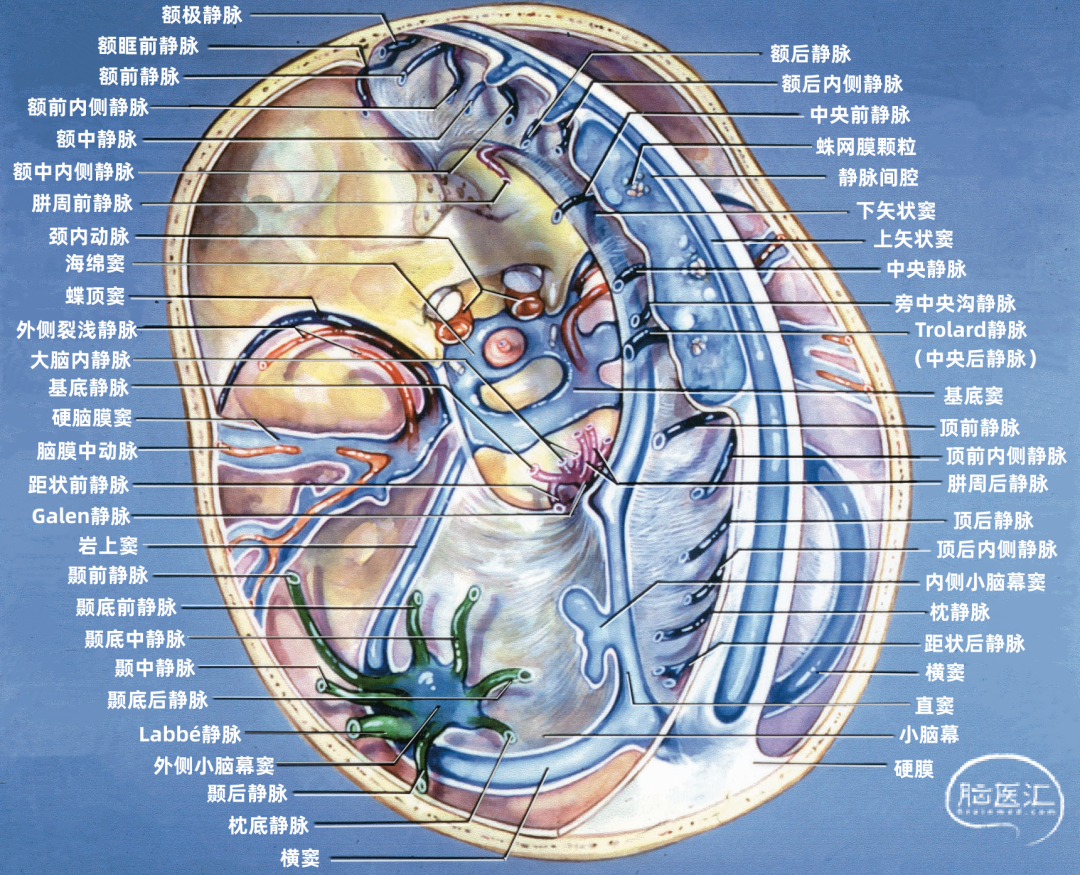

大脑的静脉可分为浅表组和深部组。浅表组引流皮层表面血液;深部组引流深部白质和灰质核团,走行于脑室壁和基底池,最终汇入大脑内静脉、基底静脉和大脑大静脉。本文仅讲解浅表组(大脑浅表静脉)。 由于大脑静脉的大小、吻合存在较多的变异,实际手术操作中有时造成较大的深部静脉主干的闭塞,但却较少引起明显的神经功能缺失,这主要归因于静脉之间存在广泛的吻合。 另一方面,有时这些复杂静脉交通网络的破坏有可能造成严重的功能障碍,如偏瘫、昏迷甚至死亡。有时静脉血管是脑深部肿瘤手术入路的主要阻碍,尤其是松果体区肿瘤,采取经颞下或经上矢状窦中部入路时尤为明显。 因为静脉大多紧贴在脑组织表面走行,而动脉与脑组织贴敷不紧,尤其在脑沟、脑池、裂隙等部位更加松散,因此静脉移位往往比动脉移位更能够提供准确的定位信息。尤其是侧脑室的静脉比动脉更能起到充当解剖标志的作用,当脑室内肿瘤造成脑室壁上各个神经组织结构边界难以辨认,更需要靠静脉血管帮助定位。二、硬膜窦

硬膜窦(sinus of dura mater) 也称硬脑膜静脉窦,是特殊的静脉结构。硬脑膜在某些部位内、外两层分开,内面覆盖一层内皮细胞,称硬膜窦。窦腔内含有静脉血,但无平滑肌,不能收缩。当硬脑膜窦损伤时,容易出血形成颅内血肿。 窦腔内无瓣膜,只在静脉注入窦腔的入口处有半月瓣、小梁和中隔等装置,这些装置起调节入窦血流量的作用。硬膜窦主要收集脑、脑膜、颅骨、眼眶和内耳等处的静脉血。此外,还引流脑脊液。 主要硬膜窦包括:上矢状窦、下矢状窦、直窦、横窦、小脑幕窦、海绵窦、蝶顶窦、蝶基底窦、蝶岩窦。▼1.上矢状窦

上矢状窦(superior sagittal sinus SSS)位于中线,引流额叶下面的前部和额叶、顶叶、枕叶外侧面及内侧面的上部。 上矢状窦的冠状切面呈三角形,左右两个侧角与覆盖半球凸面的硬脑膜相连接,下角与大脑镰相连。上矢状窦的三角形管腔前部较细,向后逐渐扩大。 上矢状窦两侧壁有的地方向外膨隆扩张,形成外侧陷窝。外侧陷窝常有大脑皮层静脉汇入,还有蛛网膜颗粒突入其中。上矢状窦的下角和外侧陷窝之间常有许多横行的纤维相连。在上矢状窦后部的窦壁内有一海绵状间隙系统,在窦壁内皮与硬脑膜之间,形成海绵状间隙,参与调节脑血流量。

下矢状窦(inferior sagittal sinus 下图)夹于大脑镰游离缘中,前方起自盲孔,向后注入直窦。下矢状窦直径为2mm左右,最短者仅19mm,长者可达110mm,平均长度70mm,其腔内无蛛网膜颗粒。主要收集大脑镰、胼胝体和扣带回附近的静脉血。

▼6.直窦

窦汇(confluence of sinuses)位于枕内隆凸平面,正中线稍偏右侧,相当于人字缝尖至枕骨大孔后唇的中点处。通常由上矢状窦与直窦在枕内隆凸处汇合而成。向左、右两侧汇入横窦。 上矢状窦和直窦的汇合方式颇多,窦汇的延续情况也各有差异。上矢状窦、直窦汇入右侧横窦者较多,约占30%。上矢状窦和直窦各分为左右支,两窦的右支合为右横窦,两窦的左支合为左横窦者占26%。而上矢状窦、直窦、枕窦及横窦汇合者占22%。▼8.横窦

横窦(transverse sinus)从枕内隆凸沿小脑幕在枕骨内侧面附着形成的浅沟向外侧走行。在岩骨嵴后方,横窦和岩上窦汇合处,横窦离开小脑幕,转向下前方,移行于乙状窦。横窦除主要收纳上矢状窦和直窦的血液外,还收纳大脑下静脉、小脑下静脉、脑干静脉、板障静脉和导静脉的血液。横窦可通过枕骨的导静脉与颅外静脉相通。 横窦于枕内隆凸附近的起点变化颇多,可以起自窦汇,也可起自上矢状窦或直窦(上图)。 上矢状窦可平均回流入左右两侧横窦,或一侧为主,或完全一侧。 右侧横窦通常较大,并接受上矢状窦的大部分引流(上图)。左侧横窦较小,主要接受直窦引流。所以,右侧的横窦、乙状窦和颈内静脉的血液主要来自大脑的浅部结构,左侧的横窦、乙状窦和颈内静脉内的血液主要来自大脑内静脉、基底静脉和大脑大静脉引流的深部结构。每侧的引流差异导致一侧或另一侧静脉回流受阻产生不同的临床症状,且左侧或右侧颈内静脉压迫产生不同的Queckenstedt's奎肯征。

颞叶外侧面的皮层静脉可引流入横窦(上图),但在流入横窦之前,它们常向内沿颞叶底面进入小脑幕的短窦,此窦进入横窦末端之前在小脑幕内走行大约1cm。来自颞叶和枕叶底面的皮层静脉通常汇入外侧小脑幕窦。 Labbé静脉通常终于横窦(上图),但也可弧形围绕大脑半球下缘汇入外侧小脑幕窦。▼9.小脑幕窦

每侧小脑幕有两个恒定但不对称的静脉窦,即内侧小脑幕窦和外侧小脑幕窦。 内侧小脑幕窦由小脑上表面的回流静脉汇聚而成。内侧小脑幕窦向内侧引流入直窦,或直窦与横窦的汇合处。 外侧小脑幕窦由颞叶和枕叶基底面和外侧面的回流静脉汇聚而成。外侧小脑幕窦起自小脑幕的外侧部分,并向外侧引流入横窦的末端。 下图示抬起小脑幕,可见来自小脑、在小脑幕下缘入窦的桥静脉。左侧黄色箭头显示一支较大的静脉自小脑上表面进入内侧小脑幕窦。右侧红色箭头显示一支粗大的来自小脑上表面的桥静脉在窦汇前方进入内侧小脑幕窦。

海绵窦(cavernous sinus)位于蝶鞍的两侧,并通过前、后海绵间窦跨越中线相连接。海绵窦状如海绵,内有许多小梁,血液可经海绵窦的间隙流过。每侧海绵窦前起眶上裂的内侧端,后抵颞骨岩部尖端,长约2cm,内外宽约1cm。上壁向内与鞍隔相移行;内侧壁上部与垂体囊相融合,下部以薄骨板与蝶窦为邻;外侧壁较厚,又分为内、 外两层,外层为致密结缔组织,内层为疏松结缔组织和网状纤维。海绵窦的冠状切面呈尖端略向下的三角形。 在前方,海绵窦与蝶顶窦和眼静脉相通;在中间,海绵窦通过经蝶骨大翼内侧面向外延伸的小静脉,穿过棘孔和卵圆孔,与翼状静脉丛相通;在后方,海绵窦直接开口于斜坡上的基底窦,并通过岩上窦连接横窦和乙状窦的交界处,通过岩下窦与乙状窦相连。▼11.岩上窦

岩上窦(superior petrosal sinus)位于小脑幕在岩骨嵴的附着处,它的内侧端连接海绵窦的后端,外侧端连接横窦和乙状窦结合处。 汇入岩上窦的桥静脉多来自小脑和脑干,而非大脑。岩上窦可经过三叉神经后根的上方、下方或周围。侧裂浅静脉有时汇入岩上窦的不常见属支(蝶岩窦)。

▼12.蝶顶窦、蝶基底窦、蝶岩窦

蝶顶窦是与脑膜动脉伴行的最大硬脑膜窦,它在翼点水平以上与脑膜中动脉的前支伴行;在此水平以下,它离开动脉经蝶骨嵴下方的硬膜汇入海绵窦前部。它的上端通过硬脑膜静脉与上矢状窦相通。蝶顶窦有可能沿蝶骨嵴向下到达中颅窝底,而不进入海绵窦前部。 蝶顶窦可以向后汇入海绵窦,沿蝶骨大翼的外侧延伸;或者通过蝶骨导静脉,穿过中颅窝底与翼状静脉丛交通;这种蝶顶窦出颅骨连接蝶骨导静脉和翼静脉丛的变异被命名为“蝶基底窦”。 蝶顶窦还可以更向后走行进入岩上窦或横窦,这种沿中颅窝底向后走行汇入岩上窦或横窦的变异被命名为“蝶岩窦”。 侧裂浅静脉通常汇入蝶顶窦;但如果蝶顶窦发育不好或缺如,则侧裂浅静脉可直接进入海绵窦,或者向下围绕颞极和颞叶底面加入蝶基底窦或蝶岩窦。三、吻合静脉

大脑外侧面最大的静脉是Trolard、Labbé、外侧裂浅静脉。 Trolard静脉是最粗大的吻合静脉,连接外侧裂静脉和上矢状窦。Labbé静脉则是连接外侧裂浅静脉和横窦的最粗大吻合静脉。外侧裂浅静脉沿外侧裂表面走行,而且主要沿蝶骨嵴汇入硬膜窦(蝶顶窦或海绵窦)。 虽然Trolard、Labbé静脉和外侧裂浅静脉大小可能相同,但更常见的是其中一支或两支血管比较粗大,而剩下的则细小甚至缺如。通常左右两侧血管的大小并不对称。

多数皮层静脉由单根起始,逐渐接受属支。相邻区域的皮层静脉可汇合成为一支桥静脉,穿出蛛网膜下腔,最后汇入硬膜窦。另外,引流半球内侧、外侧和底面的静脉,可能在交界区形成为一支桥静脉,最后汇入一个静脉窦。大脑内侧和外侧的上升静脉经常在半球上缘汇合,并进入上矢状窦;半球外侧下降的引流静脉和半球底面向外的引流静脉可在半球下缘汇合,进入颅底的硬膜窦。少数皮层静脉加入脑深部静脉系统。 相邻区域的血管间有互补关系,即某一静脉引流的区域增多,则相邻静脉的引流范围随之减少。在脑叶或面的主要引流静脉组之间也有类似的互补关系。

根据引流半球外侧面、内侧面或底面,皮层静脉分为三组。三个面的皮层静脉可依据其引流的脑叶和皮层区进一步细分。皮层静脉引流区域和方向如下: 额叶外侧面(蓝色)由额极静脉、额前静脉、额中静脉,额后静脉、中央前静脉、中央静脉、额外侧裂静脉引流。 顶叶外侧面(黄色)由中央静脉、中央后静脉、顶前静脉、顶后静脉、顶外侧裂静脉引流。 颞叶外侧面(绿色)由颞前静脉、颞中静脉、颞后静脉、颞外侧裂静脉引流。

五、引流静脉的分组

大脑浅表静脉引流皮层表面的血液,根据血管终止的位置将其分为四组: 大脑镰组汇入下矢状窦或直窦,及其属支(包括由大脑内静脉、基底静脉和大脑大静脉汇入直窦的皮层静脉)。 上矢状窦组、蝶骨嵴组、小脑幕组静脉的属支发达时,可引流大部分大脑半球。

上矢状窦组(上图 深蓝色)由回流至上矢状窦的静脉组成,包括引流额叶、顶叶、枕叶内侧、外侧面上部皮层以及额叶眶面前部的静脉。 注入上矢状窦的大脑外侧面静脉包括额极静脉、额前静脉,额中静脉、额后静脉,中央前静脉、中央静脉、顶前静脉、顶后静脉、枕静脉和Trolard静脉。 注入上矢状窦的大脑内侧面静脉(上图 蓝色)包括额前内侧静脉,额中内侧静脉、额后内侧静脉、旁中央沟静脉、顶前内侧静脉、顶后内侧静脉和距状后静脉。 一般静脉在离开软膜-蛛网膜注入上矢状窦前,会在硬膜下腔有1~2cm长的游离段。这些静脉可能直接汇入上矢状窦,也可能先汇入硬膜内的硬膜窦,再进入上矢状窦。

构成蝶骨嵴组(上图 红色)的桥静脉走行于蝶骨内表面的静脉窦。包括外侧裂浅静脉的终末支(包括额外侧裂静脉、顶外侧裂静脉和颞外侧裂静脉)和少数外侧裂深静脉,引流外侧裂附近的额叶、颞叶和顶叶的静脉血流。 这些静脉一般汇入蝶顶窦或海绵窦,少数进入蝶基底窦或蝶岩窦。 右侧的外侧裂浅静脉(下图 红色)直接进入蝶顶窦或海绵窦前部,而左侧的外侧裂浅静脉更靠后并进入海绵窦外侧部。侧裂深静脉和大脑前静脉也汇入基底静脉前端。颈内动脉行经海绵窦。中颅窝底的硬脑膜窦与脑膜中动脉伴行。

小脑幕组(上图 绿色)的桥静脉汇入行经小脑幕的静脉窦,即小脑幕窦或小脑幕附近的横窦和岩上窦。本组静脉引流颞叶外侧面和底面、枕叶的底面,包括颞底静脉、枕底静脉和来自颞叶外侧面的降静脉,如Labbé静脉。 除Labbé静脉外,这些静脉虽然有可能进入横窦,但大多数围绕半球的下缘汇聚于枕前切迹到达外侧小脑幕窦。而Labbé静脉通常汇入横窦。大脑底面的桥静脉汇入静脉窦之前,经常粘连于与中颅窝底硬膜和小脑幕表面。 从外侧面引流入小脑幕窦的静脉包括颞前静脉、颞中静脉、颞后静脉和Labbé静脉。

从下表面引流入小脑幕窦的静脉包括颞底前静脉,颞底中静脉、颞底后静脉和枕底静脉。 内侧小脑幕窦接受来自小脑的静脉血流,并加入直窦。基底窦位于斜坡。 大脑镰组(上图 紫色)由直接或经由大脑内静脉、基底静脉和大脑大静脉汇入下矢状窦或直窦的静脉构成。汇入直窦的静脉(上图 紫色)或其属支,引流胼胝体附近部分的额叶、顶叶和颞叶内侧部,此组静脉的引流区域大致相当于大脑边缘叶,包括终板旁静脉,额眶后静脉、嗅静脉、胼周前静脉、胼周后静脉,钩回静脉、海马前静脉、颞内侧静脉和距状前静脉。